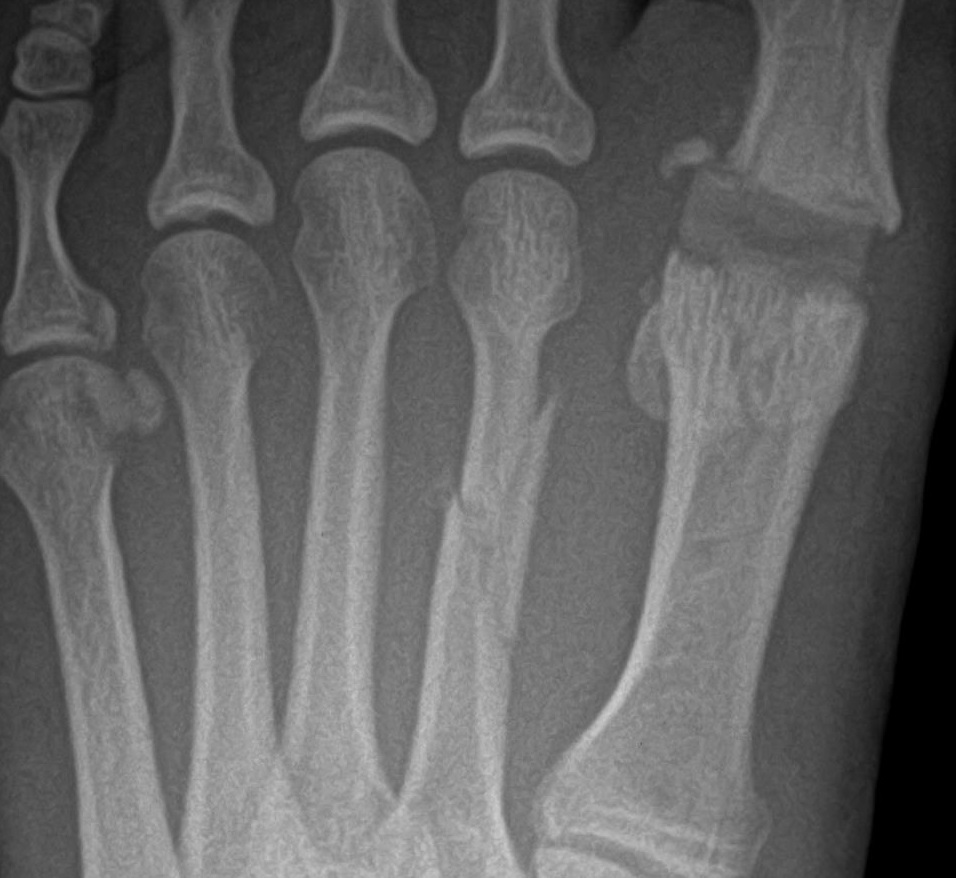

A 47-year-old male CrossFit athlete presented with pain and swelling to the dorsal left foot that he had experienced for two months prior to presenting to my office. The pain began as an ache dorsally in the foot when he was at the base of his squat and then progressed to a sharp pain with any weightbearing activity. He recalled the pain started after he felt fatigued during box jumps and did not make it up onto the box, falling forward and hitting his dorsal foot on the edge of the box. X-rays showed a displaced second metatarsal fracture with a butterfly fragment.

I recommended open reduction with internal fixation but the patient refused surgical treatment. The patient used a pneumatic walker and remained weightbearing. After three weeks, X-rays revealed minimal improvement. The patient admitted to continuing his weightbearing activities in his pneumatic walker. He wore a non-weightbearing, below-knee cast. The patient is still undergoing treatment.